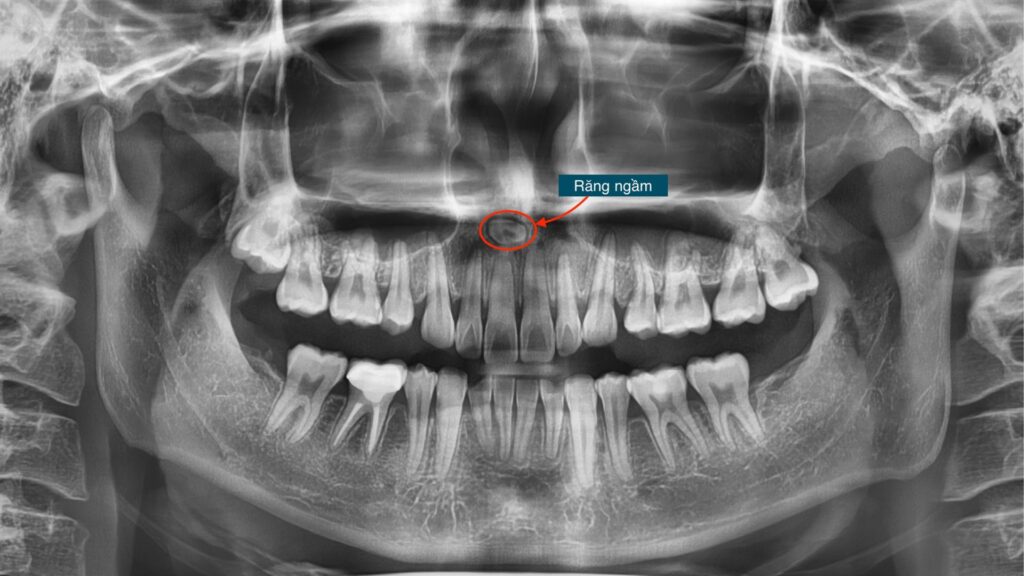

III. Răng ngầm – yếu tố then chốt thay đổi toàn bộ kế hoạch niềng răng

1. Răng ngầm và giới hạn dịch chuyển răng cửa

Nguyên nhân chính khiến kết quả thực tế không đạt như VTO là sự hiện diện của một răng ngầm tại vị trí chân răng 11. Răng này mọc theo hướng từ ngoài vào trong và nằm sát lỗ thần kinh ống răng cửa – một cấu trúc giải phẫu nhạy cảm.

Răng ngầm trở thành rào cản sinh học khiến việc kéo răng cửa vượt quá giới hạn an toàn là không thể.

2. Quyết định lâm sàng dựa trên tư duy bảo tồn

Trong tình huống này, bác sĩ đứng trước hai lựa chọn: phẫu thuật can thiệp sâu để lấy răng ngầm hoặc điều chỉnh kế hoạch niềng răng trong giới hạn sinh học cho phép. Lựa chọn cuối cùng được đưa ra dựa trên nguyên tắc bảo tồn tối đa cấu trúc sinh học và tư vấn minh bạch cho khách hàng.